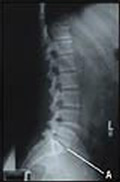

เกิดจากจุดเริ่มต้นที่มีการบิด (twisting)อย่างรุนแรงต่อหมอนกระดูก ทำให้หมอนรองกระดูกไม่แข็งแรงไม่สามารถเป็นข้อต่อที่ดีให้กับกระดูดหลัง และเกิดการอักเสบทำให้เกิดอาการปวดหลังเรื้อรัง

หมอนรองกระดูกไม่เหมือนกล้ามเนื้อที่มีเลือดและสารอาหารไปเลี้ยงมากเวลาเกิดโรคจึงหายได้เร็ว แต่หมอนรองกระดูกไม่มีเลือดไปเลี้ยงทำให้เป็นโรคเรื้องรังและอาการจะเป็นมากขึ้นเรื่อยๆ

การเสื่อมของหมอนรองกระดูกตามอายุมักจะไม่ก่อให้เกิดอาการปวดหลังเนื่องจากไม่มีการอักเสบและข้อหลังมีความมั่นคงดี